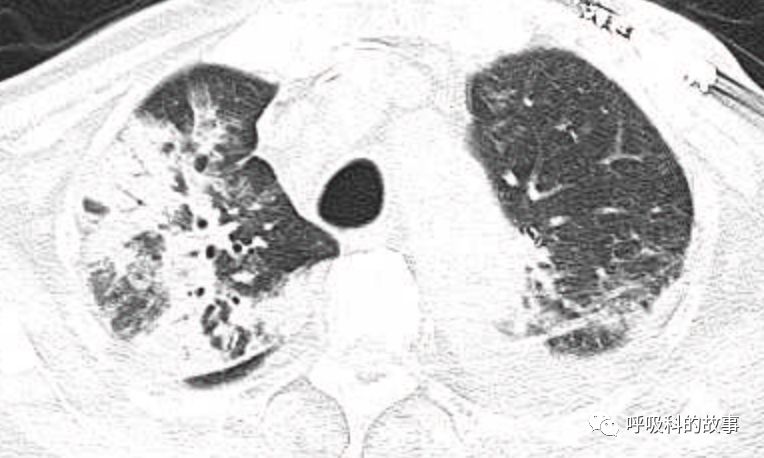

肺部CT如下:

以上的CT给我第一眼的感觉是肺炎,再结合患者有发热和血炎症指标明显增高,肺炎的诊断应该没有问题,但是胸水又是漏出液,结合脑钠肽增高和患者有胸闷气急的症状,心功能不全的诊断也能成立。在某些层面,肺部实变影以内中带为主,还要考虑肺水肿的诊断。入院后给予患者美罗培南抗感染、托拉塞米利尿治疗,以及化痰、雾化处理,患者体温在入院后三天就正常了,入院第五天复查NT-proBNP3390pg/ml;血常规示白细胞 13.5*10^9/L,中性粒细胞81.8%,淋巴细胞13.2%,超敏C-反应蛋白 25mg/L;电解质示钠 160mmol/L,氯 111mmol/L 。虽然炎症指标和心功能指标均有好转,但患者却仍旧精神差,每次查房时仍然表现嗜睡状,家属也反映患者不论白天还是夜晚多数时间不是太清醒。那么问题出在哪里呢?